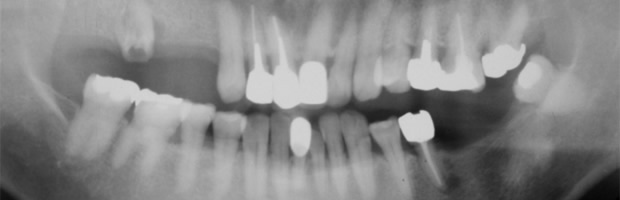

治療前のレントゲン写真です。